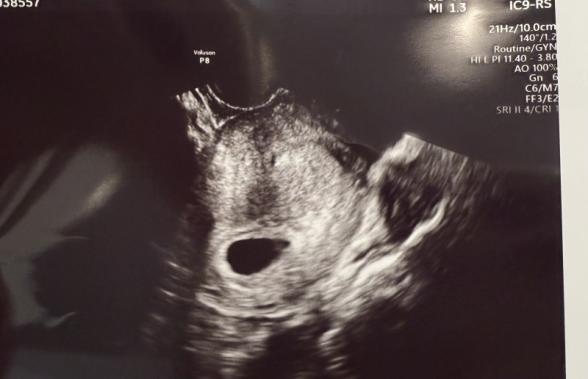

6w5dでのエコー写真です。流れ作業のような感じでエコーの最中も映像をあまり見せてもらえず、心音確認できましたとは言ってもらえたのですが、実際心音を聞かせてもらえなかったし、エコー写真を見る限り素人の私には赤ちゃんの姿が見えず、とても心配な毎日を過ごしています。他の同じぐらいの数週の方はもっと赤ちゃんが見えているのに...と次の3週間後の検診まで不安です。心音確認できたと言われて安心していいのでしょうか、赤ちゃんの写りが薄い?と今後の流産の可能性などもあるのでしょうか。コメントいただきたいです。よろしくお願いします。

健診時には特に異常の指摘はなかったものの、もらったエコーでは赤ちゃんが見えず、心拍も確認させてもらえず、ご心配になりましたね。

実際にエコーを拝見していませんので、はっきりとしたことは明言できませんが、健診で異常の指摘がなかったのでしたら、まず何かご心配なさることはないと思いますよ。ですが、やはりママさんもしっかり確認したいですよね。

妊婦健診の方が多かったりすれば、短時間で多くの方を診なければいけないので、あまり確認させてもらえないこともあるのかもしれませんが、やはり大切なことだと思いますので、次回の健診時には、赤ちゃんはどれですか?心拍を聴いてみたいです、などとお申し出いただいてもいいかもしれませんね。エコーをやりながらであれば、医師も説明しながら診てくれることもあると思いますので、ご相談なさってみてくださいね。